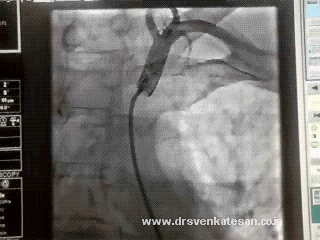

Currently selective LIMA angiogram is the gold standard.

MDCT (64 slice) gives stunning images of LIMA graft , but unfortunately , it has little value for functional assessment .

Functional assessment of LIMA graft By angiographic frame count is being attempted in our institute.Will be reported in 2012.